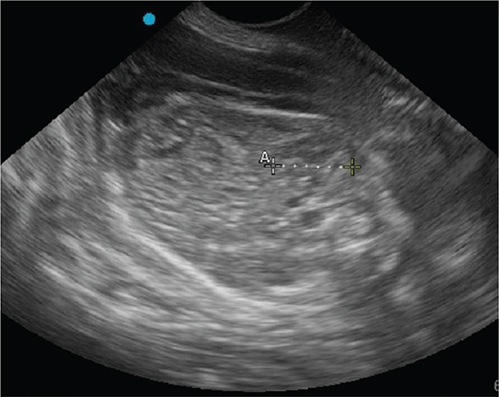

The dog was presented for an outpatient reexamination once more (on day 56 after breeding). The dog had 2 episodes of vomiting since prior visit and was trembling in the car for an hour prior to the appointment. The dog had lost 0.5 kg since prior visit, was tachycardic (160/bpm), had mild erythema of the skin and ear pinnae, and was mildly hyperthermic (39.4°C). There was continued vulvar discharge and initial mammary secretions from a few teats, consistent with colostrum. Due to the concern for systemic inflammatory response syndrome (SIRS)6 on clinical examination (elevated temperature and tachycardia), bloodwork was performed. Patient had moderate normocytic normochromic anemia of pregnancy, with a marked neutrophilia and a left shift, and mild monocytosis. A mild hypoglycemia and mild hypocalcemia were also noted (Table). Progesterone concentrations were lower (1.10 ng/ml). Targeted transabdominal ultrasonography revealed similar findings as before (multiple normal viable fetuses and 1 dead fetus [Figure 4]). Further maturation of the live fetuses was evident by slight distinction of the cortical and medullary parenchyma of fetal kidneys (Figure 5) and a more thickening of gastrointestinal tract layers in two of the fetuses7 (Figure 6). Given the patient’s deterioration and concerning laboratory findings, immediate cesarean surgery with ovariohysterectomy was again recommended; however, surgery was declined. Recommendation was made to discontinue terbutaline (Brethine®, Hikma Pharmaceuticals PLC) and altrenogest (Regu-Mate®, Merck Animal Health), to allow the dog to whelp at home. Amoxicillin and clavulanate potassium (Clavamox®, Zoetis) and ciprofloxacin (Cipro®, Bayer HealthCare Pharmaceuticals Inc.) were continued.

Fig. 5.

Figure 5. Transabdominal ultrasonographic image of a canine fetal kidney (outlined with caliper), note the degree of architectural detail indicates progression of fetal maturity.